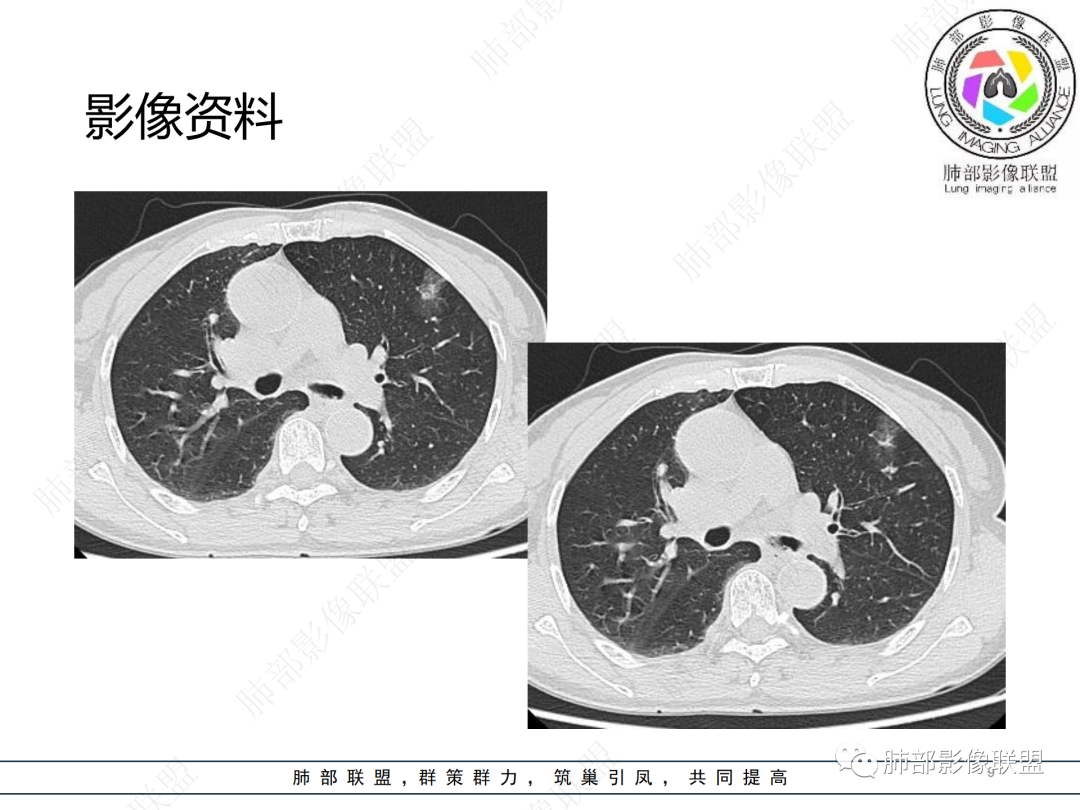

中年女性,咳嗽,胸部CT左肺上叶长条状实变影,周围磨玻璃影,边界清楚,病灶近端似乎有点状高密度影,首先考虑炎性肉芽肿,其次腺癌待排

晨读病例,中年女性,咳嗽一年,左肺上叶胸膜下三角形阴影,局部收缩,周围边缘清晰的磨玻璃影,考虑炎性病变,OP。鉴别腺癌。

左肺上叶胸膜下混合磨玻璃结节,边界似清非清,其内可见增粗血管,抗炎效果差,1年复查增大,考虑粘液腺癌,鉴别慢性炎症

左肺上叶实变影伴磨玻璃影,边界清楚,考虑腺癌,

晨读:慢性病程,胸膜下,边界似清不清,粘液腺癌。

左肺上叶磨玻璃密度,血管增粗,边界清,考虑腺,鉴别炎性

晨读,左肺上叶胸膜下混合磨玻璃密度影,内部可见血管增粗,抗炎治疗效果不佳,一年复查增大,考虑腺癌可能

晨读 左肺上叶胸膜下条片状混杂密度影,膨胀及收缩不明显,周围磨玻璃影边缘似清非清。胸膜糊墙,复查较一年前病灶增大,首先考虑粘液腺癌。

左肺上叶混合磨玻璃病灶,磨玻璃边界似清非清,病灶可见增粗血管,边缘似有月牙征,关键病史与2021年比较有增大,考虑恶性可能大,粘液腺癌、腺癌可能。鉴别慢性炎症。

老年女性,慢性咳嗽,治疗复查无效,咳少量白色粘痰,左肺上叶前段胸膜下亚实性结节,形态呈树上“蘑菇”征,并见“小圆圈”影,周边模糊的磨砂玻璃影,首选粘液腺癌,病灶定位下经皮肺穿刺活检!

晨读:患者,女,65,咳嗽1年,加重1月。胸部CT:左肺上叶胸膜下不规则mGGN,实性灶有膨隆,收缩不明显,周围磨玻璃影似清非清,内可见空泡/细支气管断面?胸膜糊墙。复查较一年前病灶增大。考虑粘液腺癌?鉴别TB、NTM。

晨读左肺上叶胸膜下结节,混合密度磨玻璃,边界似清非清,支气管腔内粘液,警惕粘液腺癌

左肺病灶,周围似清非清,考虑腺癌可能性大,鉴别炎性肉芽肿

左肺上叶混合磨玻璃结节影,部分边缘小叶间隔阻挡,周围磨玻璃影似清非清,内可见空泡,复查较一年前病灶增大。考虑粘液腺癌?鉴别炎性肉芽肿

左肺上叶前段混合磨玻璃结节,实性部分局限性凹陷,磨玻璃影边缘似清非清,老年女性,1年多胸痛病史,考虑腺癌,粘液性腺癌

肺部联盟晨读:老年女性,病程1年,混合磨玻璃密度,周围边缘较清楚,腺癌>炎症

晨读老年女性,左肺上叶胸膜下条状实变影,周围可见絮状磨玻璃影,边界较清,可见小叶间隔阻挡月牙征,抗炎无效,复查增大,考虑腺癌。

左肺上叶结节影,周围边界清楚磨玻璃影,考虑粘液腺癌

左肺上叶胸膜下混合磨玻璃结节,边界不甚清楚,抗炎无效,目前增大,考虑粘液腺癌

左肺上叶混合密度的结节,部分磨玻璃边界偏清晰,内部血管似有增粗,病灶较一年前增大,肿瘤要警惕。

左上叶混杂密度结节,边界似清非清,其内血管影增粗扭曲,年度复查增大,白色粘液痰,有树上蘑菇征?综合分析考虑结节型粘液腺癌

混合磨玻璃结节,密度不均,短毛刺,周围磨玻璃边界较清,复查病灶增大,考虑腺癌,鉴别炎性肉芽肿。

左肺上叶混合结节伴磨玻璃影,边界清楚,考虑腺癌

这个要做个重建就好了  可以整体观察这个病灶 1.边界清  2复查有增大,考虑恶性是有可能的

晨读,混合磨玻璃结节,内见增粗血管影,病史长,结节型粘液腺癌,抗炎后短期复查。